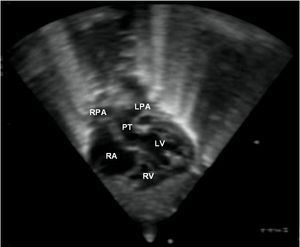

심장 초음파 검사는 심장의 구조와 기능을 정확하게 평가하는 초음파 검사이며, TGA의 특징을 보여줄 수 있다. 이 검사를 통해 TGA를 확진할 수 있다.[3]

평생 심장 전문의의 추적 관찰이 필요하다. 수술을 받은 대부분의 영아는 증상이 완화되고 정상적인 생활을 할 수 있다. 발생할 수 있는 잠재적인 합병증으로는 관상 동맥 문제, 심장 판막 문제 또는 불규칙한 심장 박동(부정맥) 등이 있다.[2]8. 추가 이미지

약어: LV 및 RV=좌심실 및 우심실, PT=폐동맥, VSD=심실 중격 결손, PS=폐동맥 협착.]]